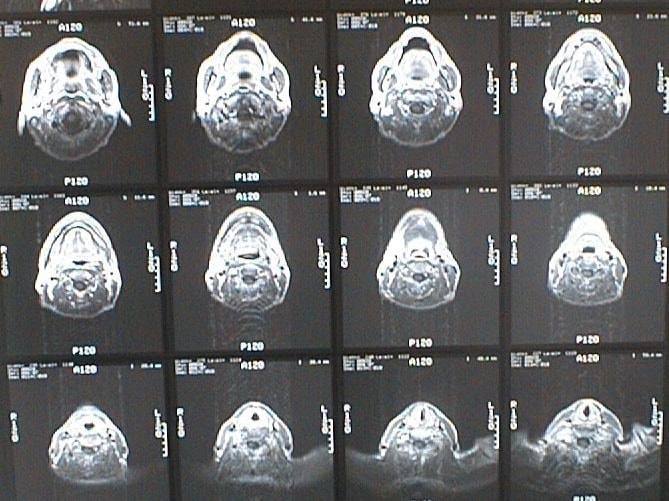

中咽頭末期がんMRI画像②

入院当時MRI画像②

中咽頭末期がん消滅時MRI画像②

入院3か月後癌消滅MRI画像②